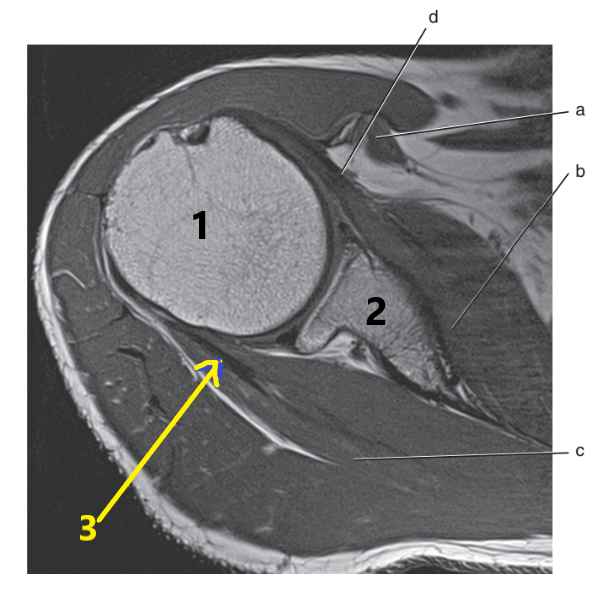

What is 1 ?

humeral head

What is c ?

anterior cruciate ligament

What is d ?

glenoid labrum

lateral meniscus

posterior cruciate ligament